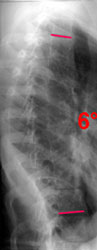

Приведен пример оценки результата оперативного лечения

в Новосибирском НИИТО больной идиопатическим сколиозом IV степени.

На рисунках слева размещены фотографии внешнего вида и рентгенограммы пациентки до и после хирургического лечения, что до недавнего времени позволяло судить

о эффективности операции. Основным количественным критерием при этом была величина коррекции деформации позвоночника по углу Кобба,

До операции: угол по Коббу 64°, PTI=2,8